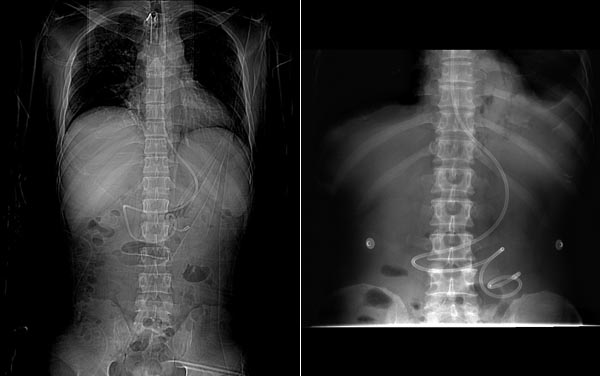

螺旋型鼻肠管

陈纯波、叶珩副主任医师课题组在国内率先开展螺旋型鼻肠管的规范化应用研究,在广东省科技计划项目、广东省医学科学研究基金项目的支持下,已累计完成400余例危重患者的置管。在前期研究的基础上,提出螺旋型鼻肠管的规范化应用流程。即选择APACHEⅡ评分≤20分,且未应用镇静剂、肌松剂及缩血管药的重症患者,置管后常规使用胃复安、红霉素或多潘立酮等促胃肠动力药,对观察24小时管端仍无法自动通过幽门的少部分患者,则进行床边补救性手法插管,规范化应用的总体成功率90%以上,在国内居先进地位。